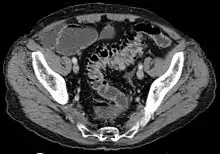

- على النقيض؛ الأشعة المقطعية هي الاختبار الأمثل في حالات النوبات الحادة لالتهاب الرتج وعند وجود مضاعفات.[39]